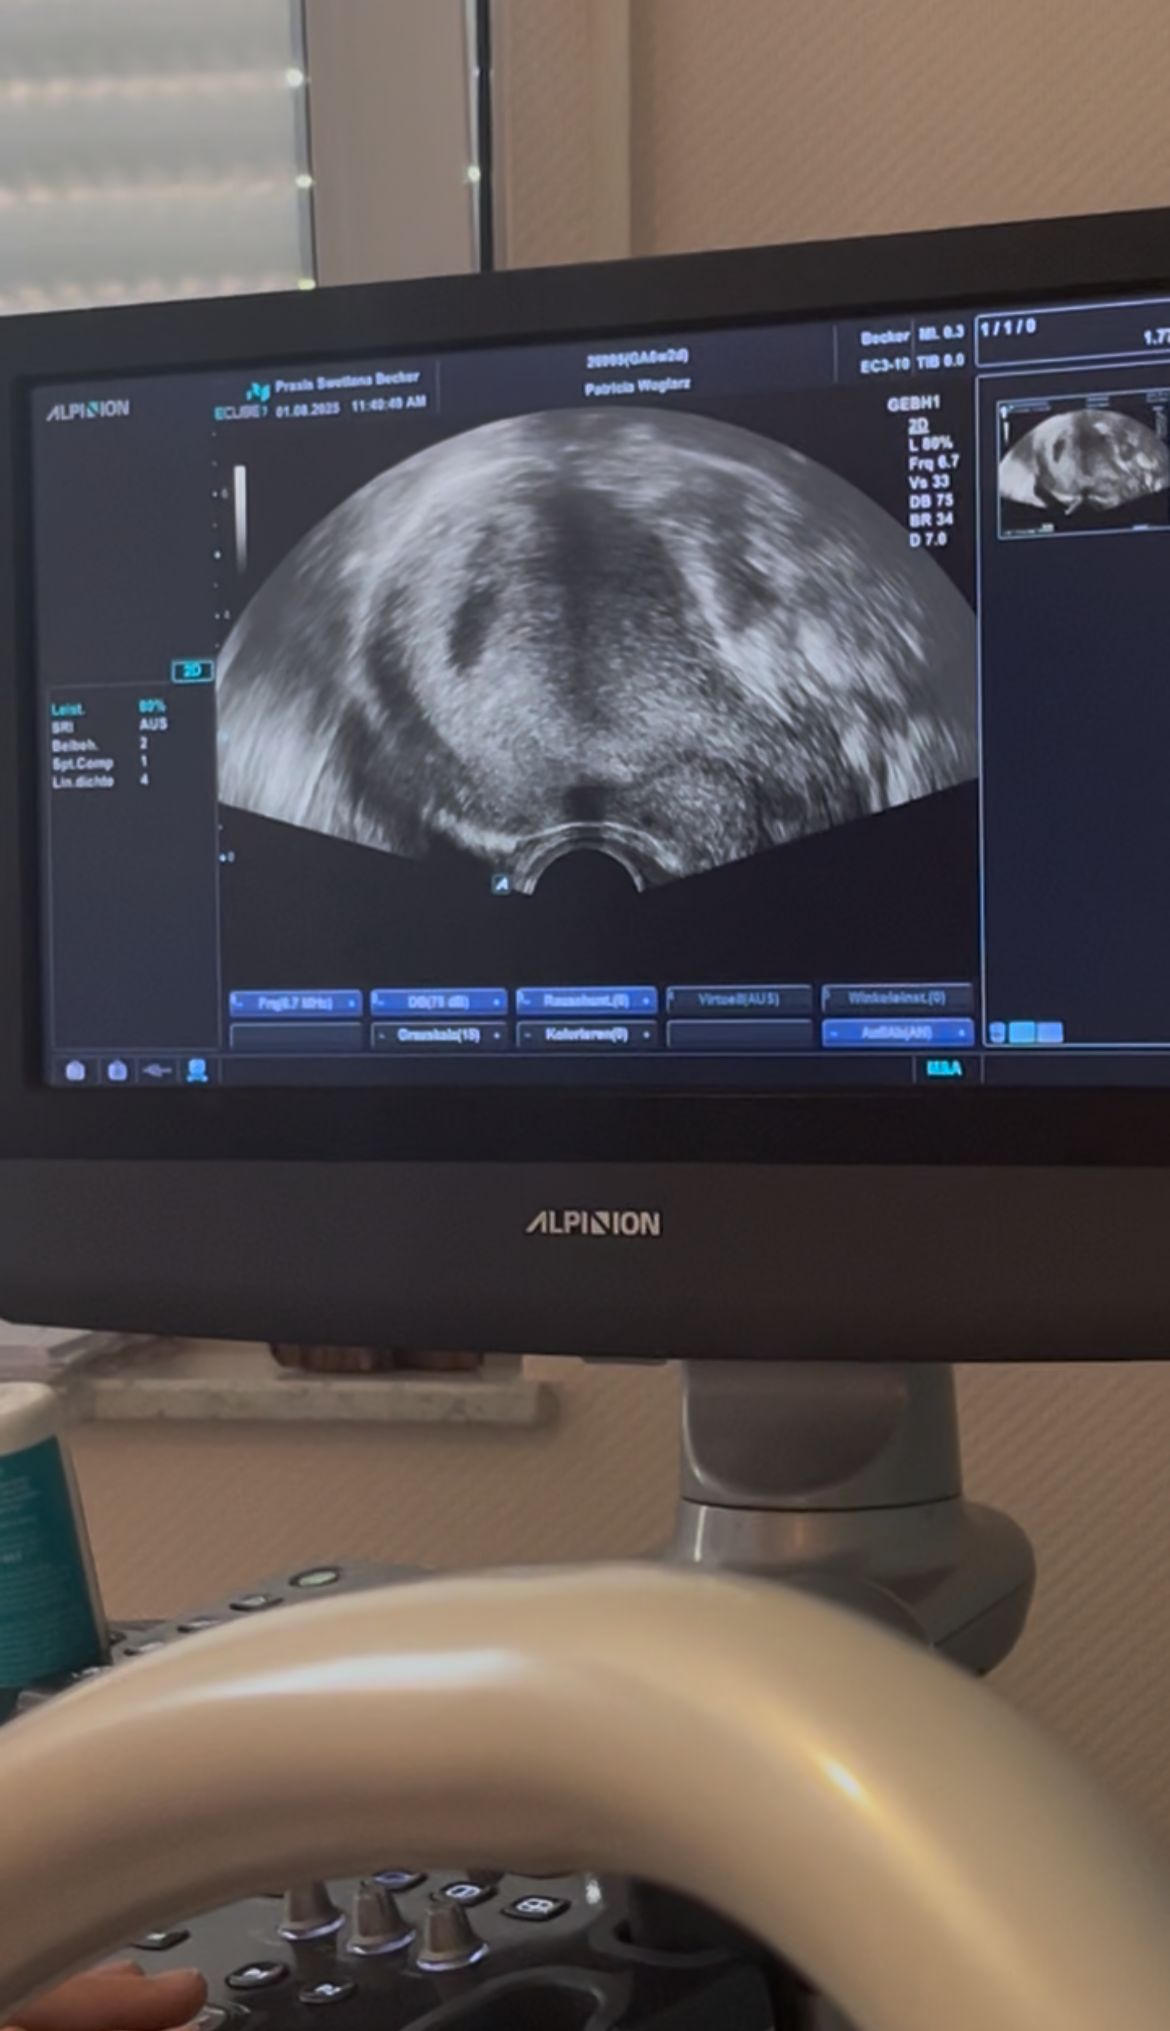

Symbolbild